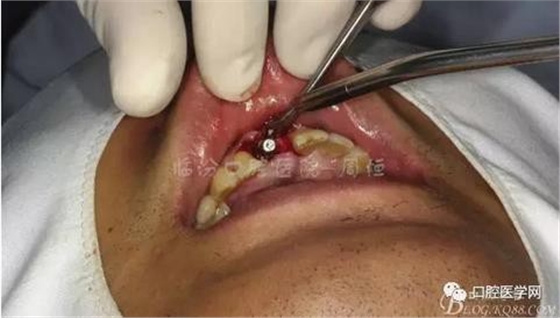

圖5 拔除殘根

圖6 術(shù)中植入植體